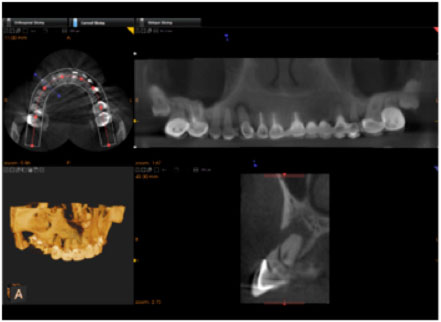

Endodontists have long dreamed about being able to visualize, in 3 Dimensions, the area to be diagnosed and treated. Well, that day has arrived. In our office, we are fortunate to have one of the only Carestream Dental 9000 3D Cone Beam Computed Tomography (CBCT) Systems in Central New York. The 9000 3D Extraoral Imaging System boasts the highest resolution and lowest radiation in its class. This system allows capture of clear, detailed, anatomically correct 3D images in seconds.

Within our practice we have found that a CBCT scan often allows us to see areas that were previously hidden when examining conventional films alone. Because we firmly believe that through the use of CBCT scans we are able to provide better care to our patients than what was possible prior to the introduction of the CBCT technology, we would like all of our patients who have conditions that may benefit from a CBCT scan to be able to have access to the scan.